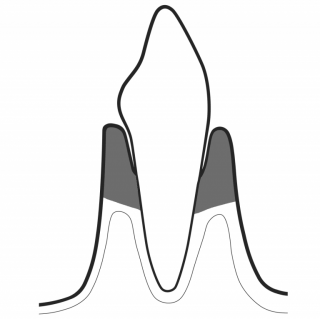

PRESERVE HEALTHY TEETH

GBT minimizes the use of power and hand instrumentation. AIRFLOW® is minimally invasive on all types of dental tissues: dentine, cementum, enamel and gums. Minimal abrasion for maximum comfort: GBT enables the patient to enjoy natural teeth and implants for much longer.

PREVENT CARIES

Biofilm is not always visible to the naked eye. Disclosing biofilm helps to remove all biofilm. GBT prevents caries and gum disease in children and adults. No biofilm = No caries.

DETECT CARIES AT AN EARLY STAGE

Caries often develop in areas not accessible by rubber cups or brushes, such as interdental areas, pits and fissures. AIRFLOW® cleans it all. A final check delivers a more accurate, precise and early detection of caries on clean surfaces. Also, it allows fluoride to access a clean tooth more easily.

PRESERVE HEALTHY SOFT TISSUES

GBT step 04 AIRFLOW® removes biofilm in a minimally invasive way. AIRFLOW® PLUS Powder is proven to be gentle on the gingiva and other soft tissues. In contrast, rotary and hand instruments may cause damage.

TREAT GINGIVITIS

AIRFLOW® PLUS Powder easily and safely removes biofilm and early calculus from coronal surfaces and sulcus. The PIEZON® PS NO PAIN Instrument removes the remaining calculus in a minimally invasive way.

TREAT PERIODONTITIS

PERIOFLOW® with PLUS Powder preserves cementum during periodontal maintenance. It effectively removes subgingival biofilm in residual deep pockets. The PIEZON® PS NO PAIN Instrument removes the remaining calculus in a minimally invasive way. Final check ensures that no calculus remains.